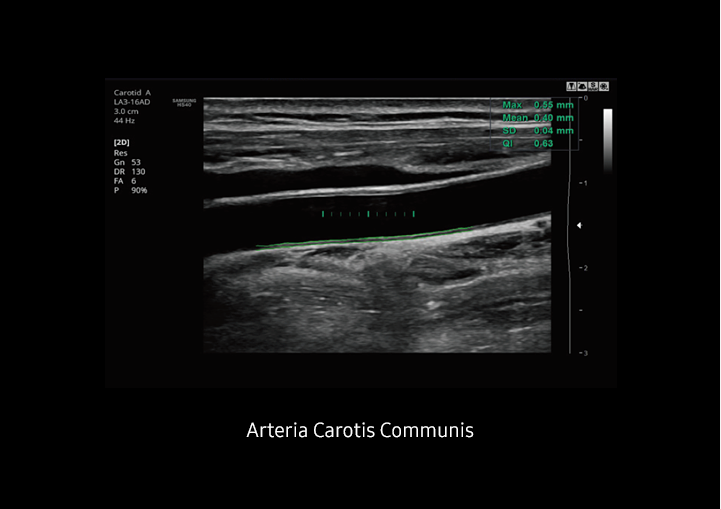

Auto IMT

Auto IMT+™ ermöglicht Ihnen die automatische Messung der Intima-Media-Dicke der Arteria Carotis Communis für die Analyse von Schlaganfall- und Herzinfarktrisiken. Die einfache Bedienung hilft Ihnen, Ihren Workflow sowie auch Ihren Patientendurchsatz zu erhöhen. Dieses einfache Verfahren verbessert die Produktivität Ihrer Untersuchungen unter Hinzufügung diagnostischer Zusatzinformationen.

Auto IMT+™